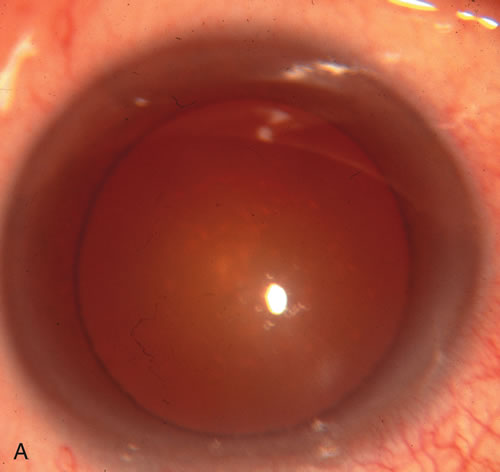

CATARACT EXTRACTION ALONE REDUCES IOP IN MOST EYES WITH ANGLE-CLOSURE GLAUCOMA

Uncomplicated cataract extraction substantially reduces IOP, along with the number of postoperative glaucoma medications in eyes with angle-closure glaucoma.146,147 When preoperative gonioscopy reveals PAS, along with adjacent areas of appositional closure, lens extraction alone in select cases may be a reasonable alternative to filtration surgery.148,149 Phacomorphic angle-closure disease due to enlargement of the lens with progressive angle crowding is eliminated following lens extraction. The width and depth of the anterior chamber angle in eyes with angle-closure glaucoma increases significantly after cataract extraction with IOL implantation and becomes similar to open-angle glaucoma and normal eyes.150,151 (Fig. 5). Combining phacoemulsification, IOL implantation, and limited goniosynechialysis is effective in the treatment of cataract and chronic angle-closure glaucoma.152 Phacoemulsification with implantation of a foldable IOL is more effective in reducing IOP and improving visual acuity than surgical peripheral iridectomy in eyes with acute angle-closure glaucoma.153

Fig. 5. Anterior chamber angle changes associated with lens extraction and PCIOL This 65-year-old Vietnamese woman has a long-standing history of chronic angle-closure glaucoma treated with laser peripheral iridectomy. The optic nerve demonstrated mild glaucomatous damage and IOP was moderately controlled on two antiglaucoma medications. The cataract was removed through temporal clear corneal phacoemulsification with foldable acrylic IOL. A. Symptomatic cataract in narrow-angle glaucoma eye with patent iridectomy. B. Intraoperative goniophotograph showing crowding of angle with increasing narrowness due to phacomorphic component. C. Intraoperative photograph showing temporal clear corneal approach with IOL in the capsular bag. D. Intraoperative goniophotograph demonstrating deepening of chamber angle following lens extraction. Proposed theories for IOP reduction following lens extraction with complete wound closure:

1. Anterior chamber deepening with improved access to trabecular meshwork

2. Increase in traction on the trabecular meshwork

3. Improved outflow facility mediated by an increase in prostaglandin release

4. Reduction in aqueous humor production

5. Atrophy of ciliary body processes

6. Goniosynechialysis due to intraoperative over deepening of AC with viscoelastic

7. Relief of undiagnosed pupil block